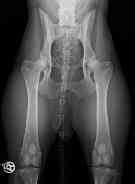

| Vom

Wellensittich bis zum Bernhardiner - vom Zahn bis zur Hüfte

können und müssen scharfe

und kontrastreiche

"Standbilder" angefertigt werden. |

| Zugelassene

Röntgenstelle für HD

(Hüftgelenksdysplasie), ED

(Ellenbogengelenksdysplaie) und OCD

(Osteochondrosis dissecans). |